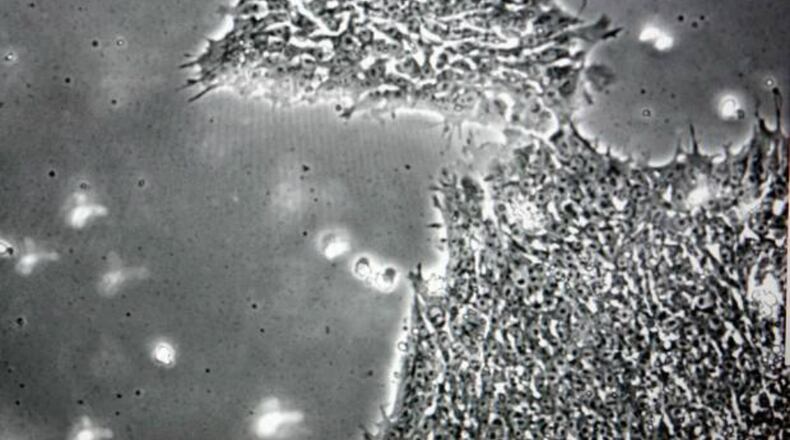

Discovery of the algae virus was an offshoot as scientists were looking at microbes that live in the human throat.

Nearly half the patients in the study tested positive for the virus. Doctors say that group didn’t do as well in tests measuring speed and accuracy in visual processing. They also had shorter attention spans.

However, they contend this work proves some can leave a person physically healthy, but cause them to struggle mentally.